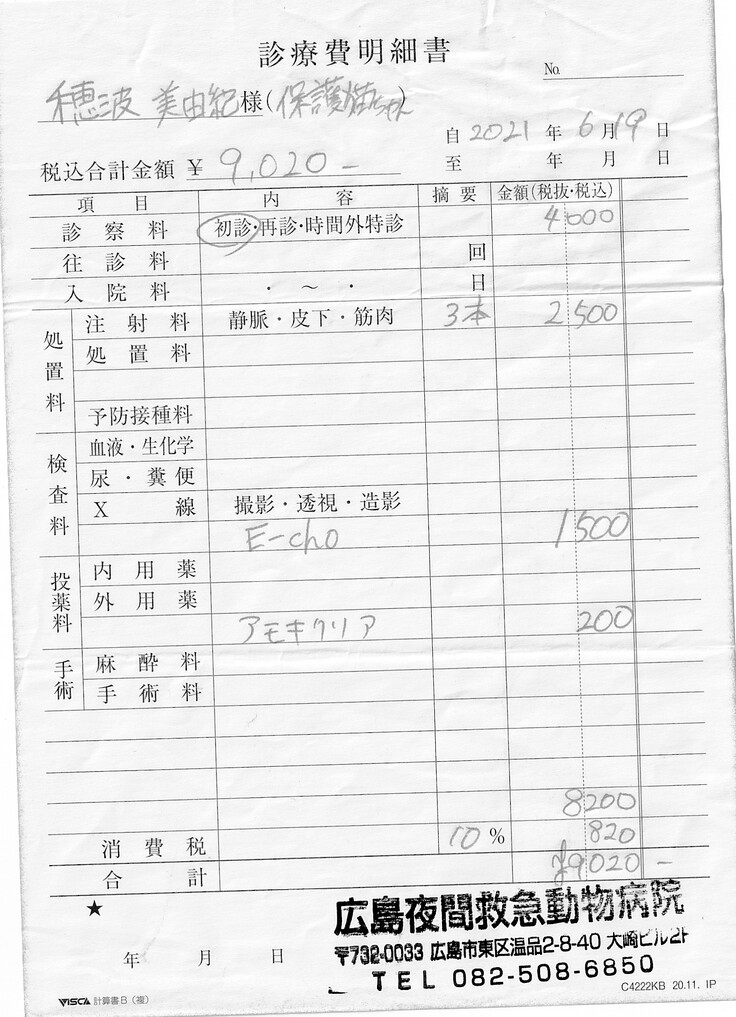

明細書

①入院費用